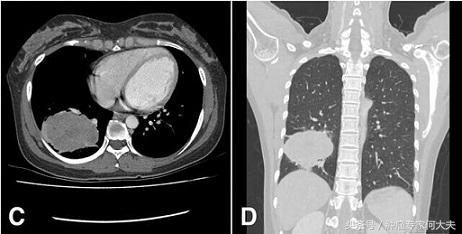

不幸得癌症怎么办,不幸确诊了肺癌要积极治疗 今日上午,接到一个咨询电话,病人老张家是江西农村的,男性,68岁,一月前因持续发热,被确诊为右肺腺癌,纵膈、肺门淋巴结转移,单侧胸腔积液。病人儿子小张在上海打工多年,因此就把父亲的病情资料带到上海市多家医院咨询治疗方案,大致意见就是建议住院,做全身PET-CT,若无远处转移,先新辅助化疗,再考虑可否手术,同时建议进行基因检测,这一系列下来差不多得十万左右。小张告诉我说,他问上海医生,他花这么多钱,能彻底治好吗?医生说不一定!于是,小张就慌了神。到底这个钱花不花?